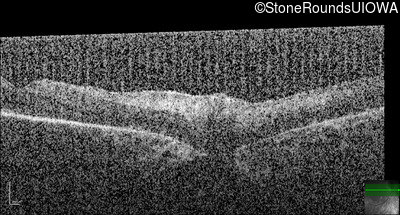

Optical Coherence Tomography - Right -

No Light Perception

Optical Coherence Tomography - Left -

Light Perception